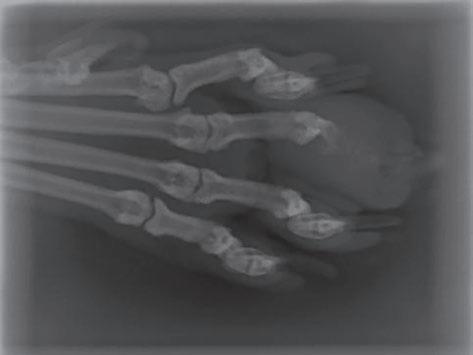

• Síndrome dígito-pulmonar felino como consecuencia de metástasis de neoplasias pulmonares primarias